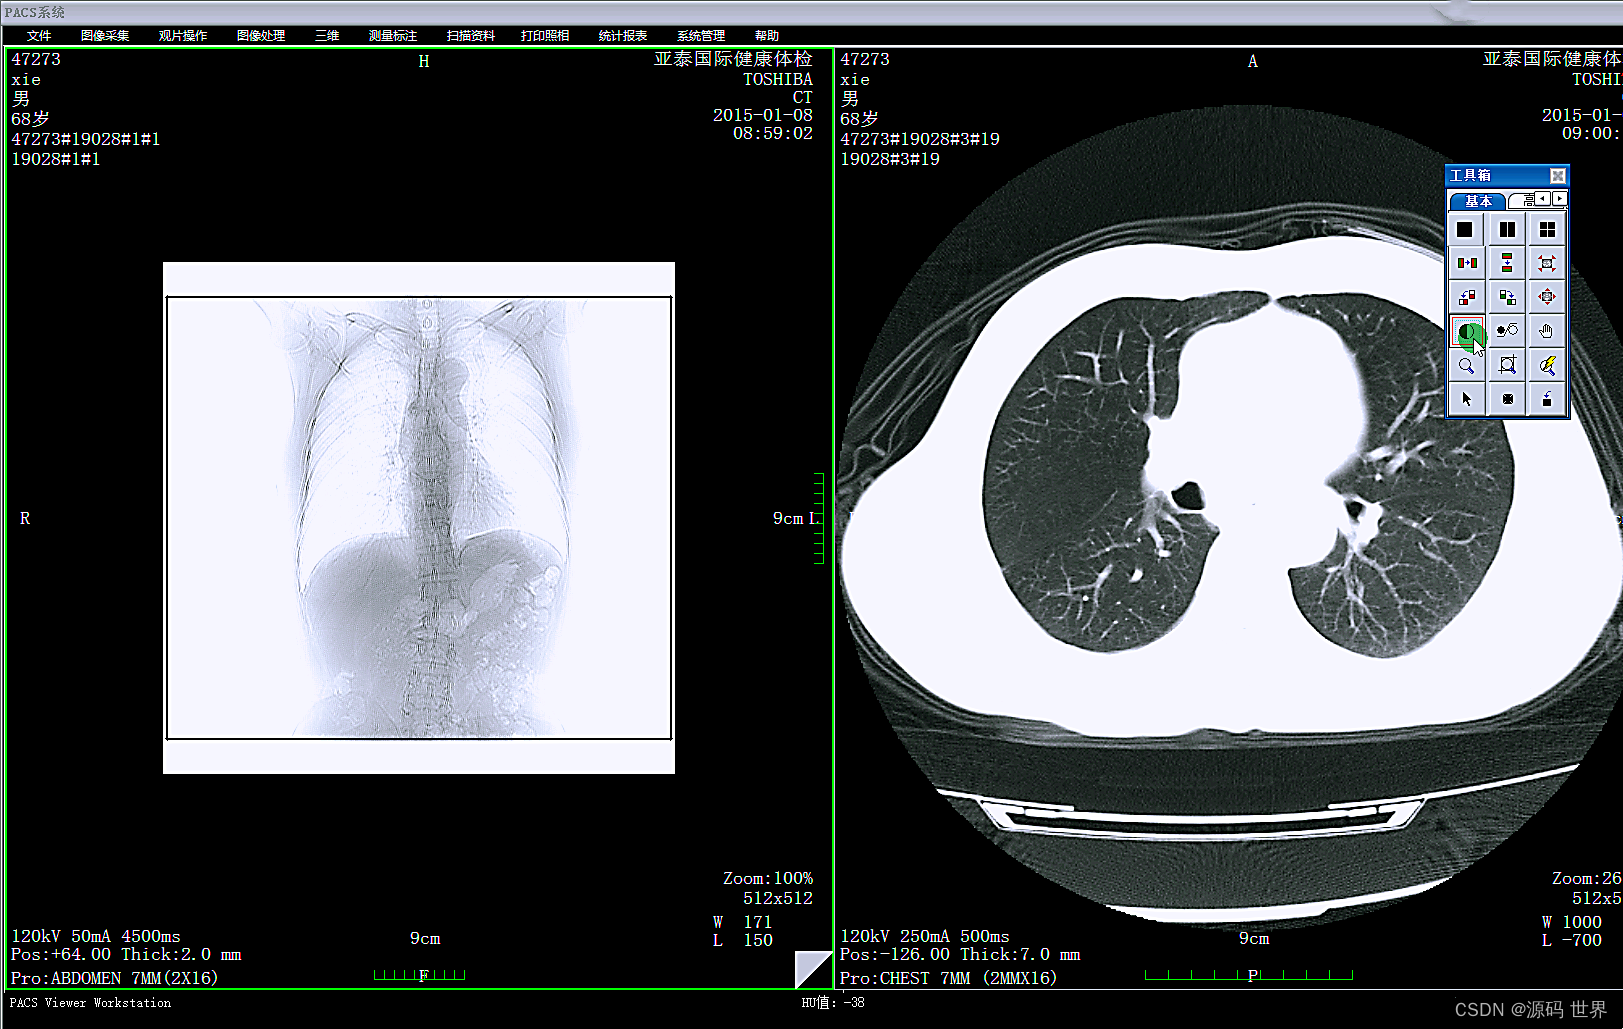

PACS系统的作用

影像归档与通信系统(PACS)则专注于影像资料的存储、检索、分发和通信。PACS系统可以联接不同的影像设备(如CT、MR、XRAY、超声、核医学等),存储和管理图像,以及图像的调用与后处理。PACS系统也可以与其他系统如HIS、RIS集成,以提高工作效率和检查准确性。